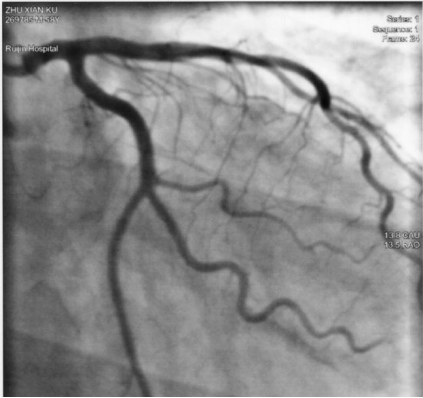

近一個世紀來,隨著解剖學,放射診斷學,材料科學...等的發(fā)展,心臟介入技術也出現(xiàn)了翻天覆地的變化,各種鞘管,導絲,導管, 球囊, 支架,換瓣, 搭橋等新技術的應用日益廣泛并趨于成熟,隨著生產(chǎn)工藝的改進,導絲,導管等越來越精細,配套的醫(yī)療器械也日趨完善, 比如利于導絲進入的Y型連接閥,球囊擴張用的壓力泵,方便輸液或造影劑輸入選擇的三通,術后的壓迫止血袋等, 即使位于冠脈小分枝的病變也可以得到矯正。 這里簡單介紹下心臟介入中常用的造影導管和指引導管。

功能上造影導管主要是將造影劑注入到冠狀動脈,起診斷目的。而指引導管目的是導入起治療作用的導絲, 球囊, 支架等設備。他們基本上都由三層結構組成: 外層:特殊的聚乙烯塑料材質(zhì),與導管的形狀、硬度及與血管內(nèi)膜的摩擦力有關;中層:鋼絲編織結構,保證導管不會塌陷并抗折斷;內(nèi)層:尼龍PTFE涂層。起一定潤滑作用, 可減少造影劑,導絲, 球囊或其它器械通過時的摩擦力。

為了更好的進入血管,造影導管與指引導管的頭端設計成不同形狀而用于不同的冠狀動脈分枝。如下圖所示: